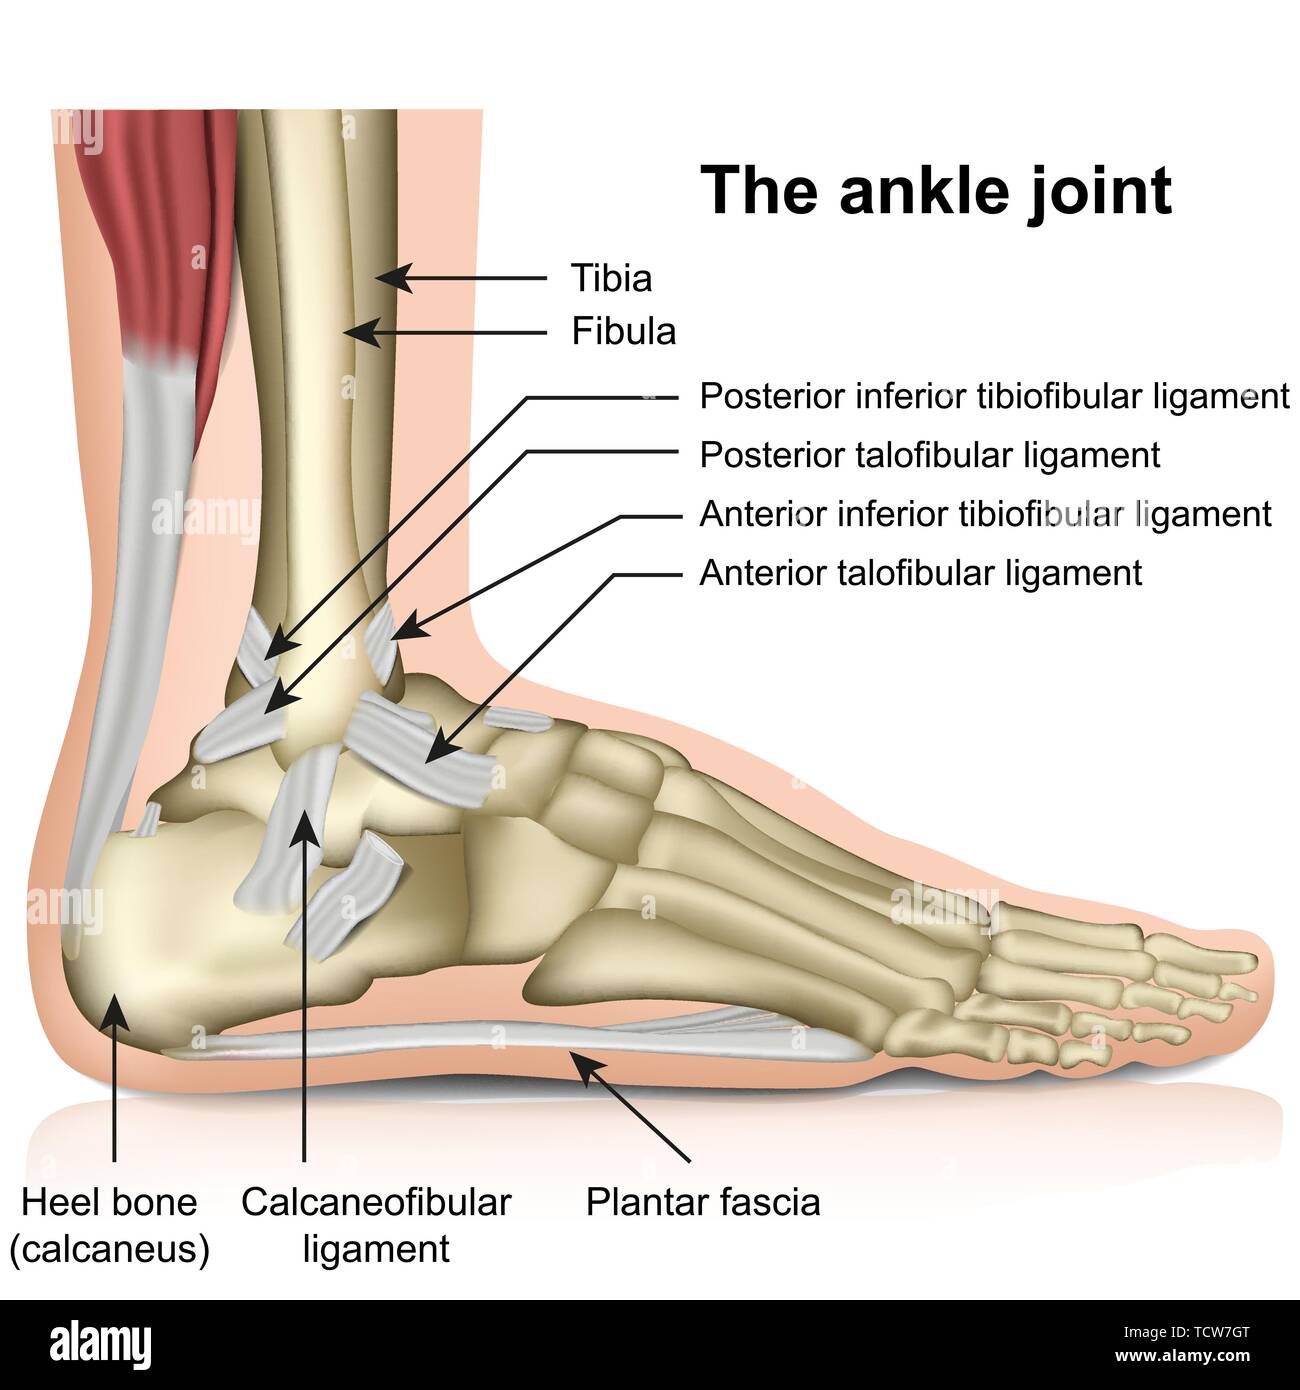

RFTCW7GT–L'articulation de la cheville, les tendons de la cheville anatomie pied eps vector illustration infographie 10